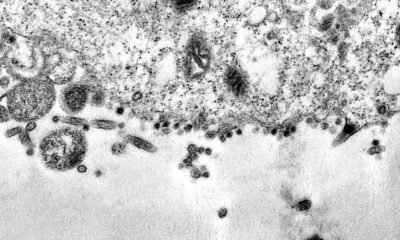

Pesquisadores do Instituto de Biologia da Universidade do Estado do Rio de Janeiro (Uerj) desenvolveram um equipamento para capturar e medir a carga de coronavírus em...